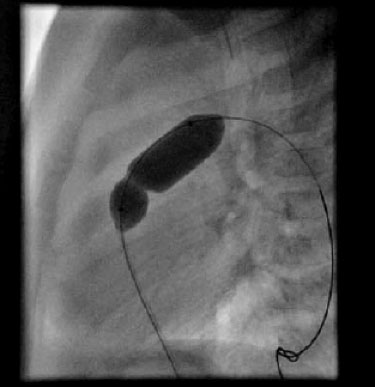

An intravenous drip of prostaglandin E1 is initially administered to maintain the patent ductus arteriosus and improve oxygenation (dose: 0.01-0.1 µg/kg/min), and maintenance of the acid-base balance, temperature, and correction of hypoglycaemia are all essential. In new-borns that areseverely cyanotic or acidotic after the perfusion of prostaglandin E1,balloon atrial septostomy (or Rashkind’s procedure) should be performed for stabilization. It is currently performed in the neonatal unit, under echocardiographic control (in some hospitals it is still performed in the Low Hemodynamics Unit control by fluoroscopy, but it requires the transfer of a new-born which is usually hemodynamically unstable). It consists of the introduction of a specific catheter which has a balloon that is inflated on the left atrial side which, when stretched, causes a rupture of the septum of the fossaovalis, creating an atrial septal defect.